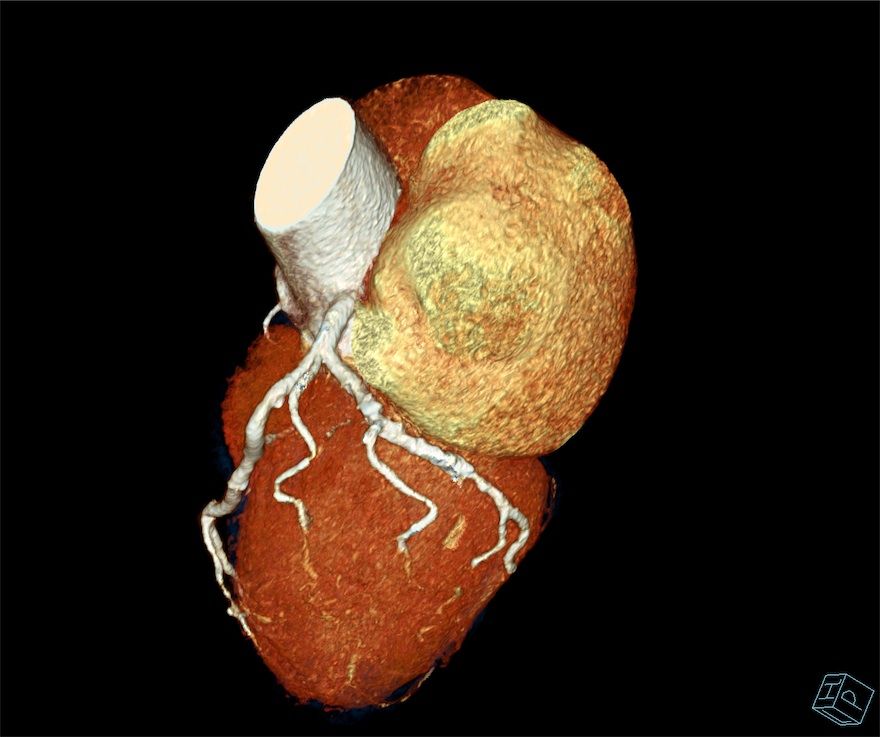

Cardiac CT

CARDIAC CT. Explained.